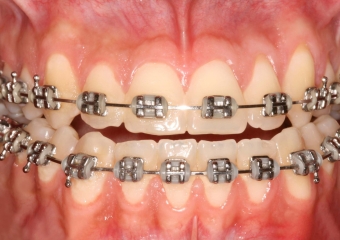

Mordida final